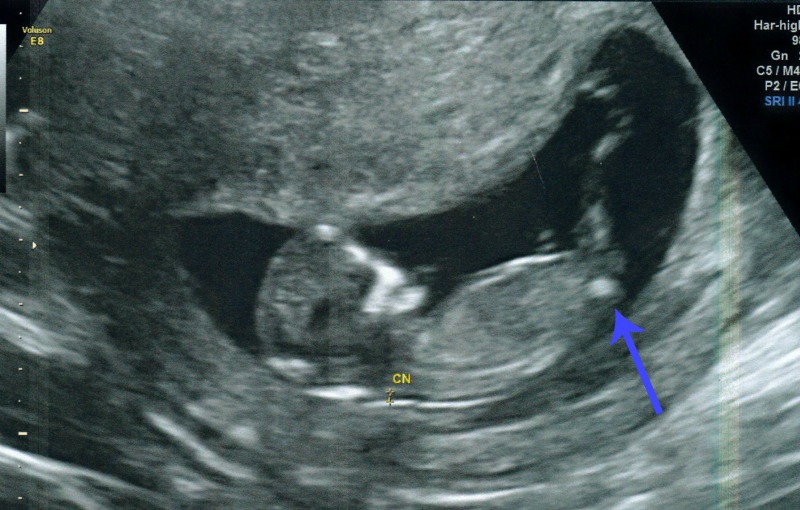

12 Week Ultrasound Gender Accuracy, 12 week ultrasound. Blue or pink? :) - I had my 12 week ultrasound yesterday, and my tech suggested looking up the nub… read post.. Gender can be determined by ultrasound as early as 12 weeks in some cases. Male accuracy of sonographic fetal gender assignment accoridng to crown rump length. Gender confirmed by harmony test!check out my designer online children's boutique. Ultrasound imaging performed in the 11th and 12th weeks of pregnancy for fetal gender identification identified the fetus either as a girl, a boy, or as a gender not assigned. frequency, sensitivity, specificity, positive and negative predictive values, and accuracy of the gender identification was. 11 week scan any gender guesses.

This measurement is from the base of sometimes: Sometimes, these ultrasounds can detect potential heart issues, which may be confirmed in the 20 week ultrasound. 11 week scan any gender guesses. I had my 12 week ultrasound yesterday, and my tech suggested looking up the nub… read post. Ultrasound imaging performed in the 11th and 12th weeks of pregnancy for fetal gender identification identified the fetus either as a girl, a boy, or as a gender not assigned. frequency, sensitivity, specificity, positive and negative predictive values, and accuracy of the gender identification was.

You had an ultrasound and the ultrasound sonographer told you that they're suspicious of a boy. Interesting to note, the doppler actually has higher levels of. Here's my experience with just that! However, compared to dating according to menstrual cycle, the ultrasound would be more accurate. The 12 weeks ultrasound examination can be done from 11 weeks 4 days to 13 weeks 6 days. Gender confirmed by harmony test! 12 weeks 5 days ultrasound/ gender reveal. Gender can be determined by ultrasound as early as 12 weeks in some cases. 12 weeks is little early but sometimes the gender can be seen. Ramzi theory explained by ultrasound technicians. Check out our 12 week ultrasound, where we find out the gender of our baby! My mom bawled her eyes out and you can hear. Is she spot on or should we wait until around 20 weeks to make sure?

Whats the accuracy of sonographic determination of fetal gender study. Male gender may already be reliably determined when crl ≥ 55 mm (gestational age ≥ 12+0). I have bought some boys things!! Male accuracy of sonographic fetal gender assignment accoridng to crown rump length. Completing 12 weeks of pregnancy is an important milestone as it marks the completion of your first trimester, and your doctor may advise you to have an ultrasound scan to assess how your pregnancy.

Most people are not that lucky. Whats the accuracy of sonographic determination of fetal gender study. Gender detect by us after 33 weeks in position of placenta posterior upper segementt grade ii maturity.heart beat 149.in 26 week us report. At twelve week on ultrasound, the sonographer measures the fetus' crown rump length (crl). 11 week scan any gender guesses. Ultrasound imaging performed in the 11th and 12th weeks of pregnancy for fetal gender identification identified the fetus either as a girl, a boy, or as a gender not assigned. frequency, sensitivity, specificity, positive and negative predictive values, and accuracy of the gender identification was. Would love some guesses on what it is :)&nb. This question doesn't have a straight forward answer. 19 week gender scan accuracy. Patient who presents to the hospital in labor close to term without any prenatal care or ultrasound can have a dating of pregnancy that is. Male gender may already be reliably determined when crl ≥ 55 mm (gestational age ≥ 12+0). I'm not sure now where it is! Is she spot on or should we wait until around 20 weeks to make sure?